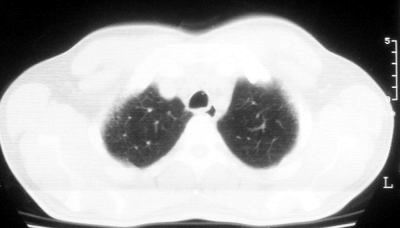

1\\粟粒性肺结核可能性大,支气管肺泡癌不排除

双肺散在小结节影,考虑粟粒性肺结核.肺窗薄扫会更好看些.

考虑粟粒性肺结核

双肺外侧带胸膜下可见网状阴影,考虑轻度肺间质纤维化。

双肺纹理增强并可见网格状影达外带,考虑双肺感染并轻度间质纤维化

1.双肺急性粟粒型肺结核;2.少量腹水.

就这图像考虑间质性肺炎。

肺间质纤维化并肺部感染,结合不能排出,毕竟糖尿病人易合并之,建议结合ppd检查或hrct进一步扫描。